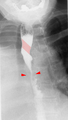

Tape-like impression of the esophagus caused by aberrant subclavian artery. Below (arrows) narrowing of the esophagus by a tumor that is causing the swallowing problems.